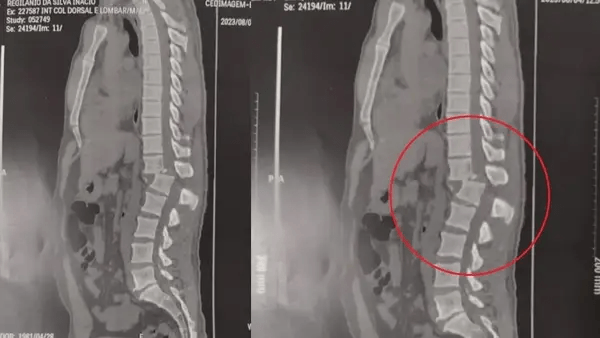

A confiança da família na recuperação se deve ao sucesso do procedimento cirúrgico, que já deu a Regilânio uma vitória: nesta terça-feira ele conseguiu sentar pela primeira vez. Duas imagens de raio-x  mostram o antes e depois da cirurgia. A primeira, feita antes do procedimento, revela a coluna vertebral do paciente fraturada entre as vértebras T12 (fim da parte torácica) e L1 (início da parte lombar). Já na segunda imagem é possível verificar que a região voltou a ficar alinhada.